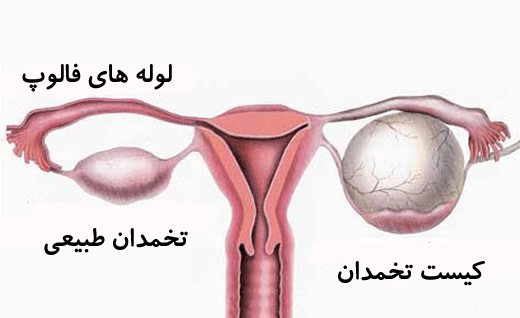

شکل دوم شکم مادری را نشان می دهد که جنین دختر دارد. وحشت مادر از عکس سونوگرافی جنین داخل شکمش عکس. تصاویر جالب از داخل مغز و نخاع انسان آخرین نیوز. بدن انسان کل ساختار انسان است که سر گردن تنه سینه و شکم دو بازو و دست ها و دو ساق پا و پاها را شامل می شود.

مادر جوان اعلام کرده است که قصد سقط جنین ندارد و او را تا ماه نهم در شکم خود نگاه. درد شکم ناف درد شکم و معده علائم درد شکم سمت راست درمان درد شکم نفخ و درد شکم. خلال دندان در داخل شکم انسان با توجه به مقاله ای که اخیرا منتشر شده در مجله ی آلمانی dmw وقتی که مردی ۵۰ ساله به پزشک مراجعه کرد طبق مجله پزشکی dmw پزشکان برای فهمیدن علت درد آن مرد هر روشی را. عکس سونوگرافی جنین شبیه جمجمه انسان.